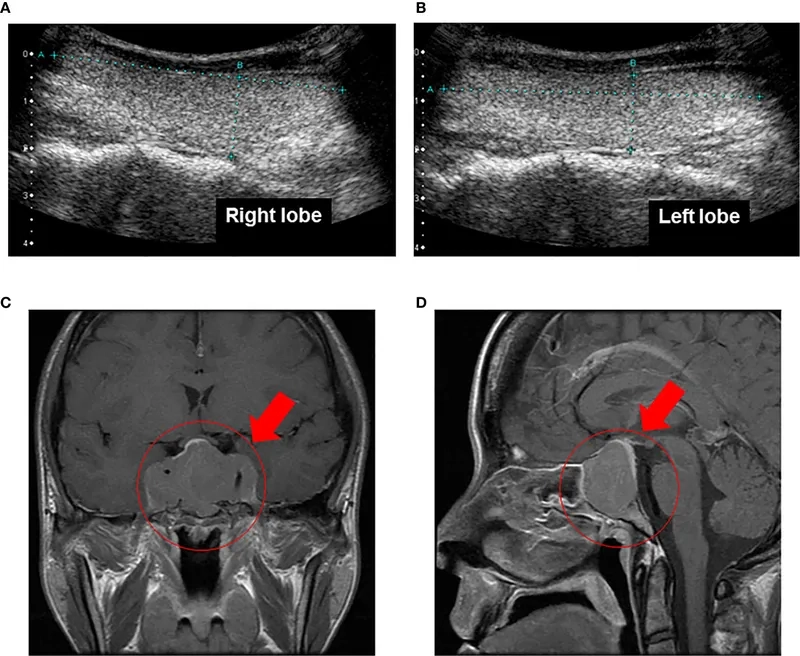

The top pituitary tumors images everyone is searching for

Close-up image of a pituitary adenoma